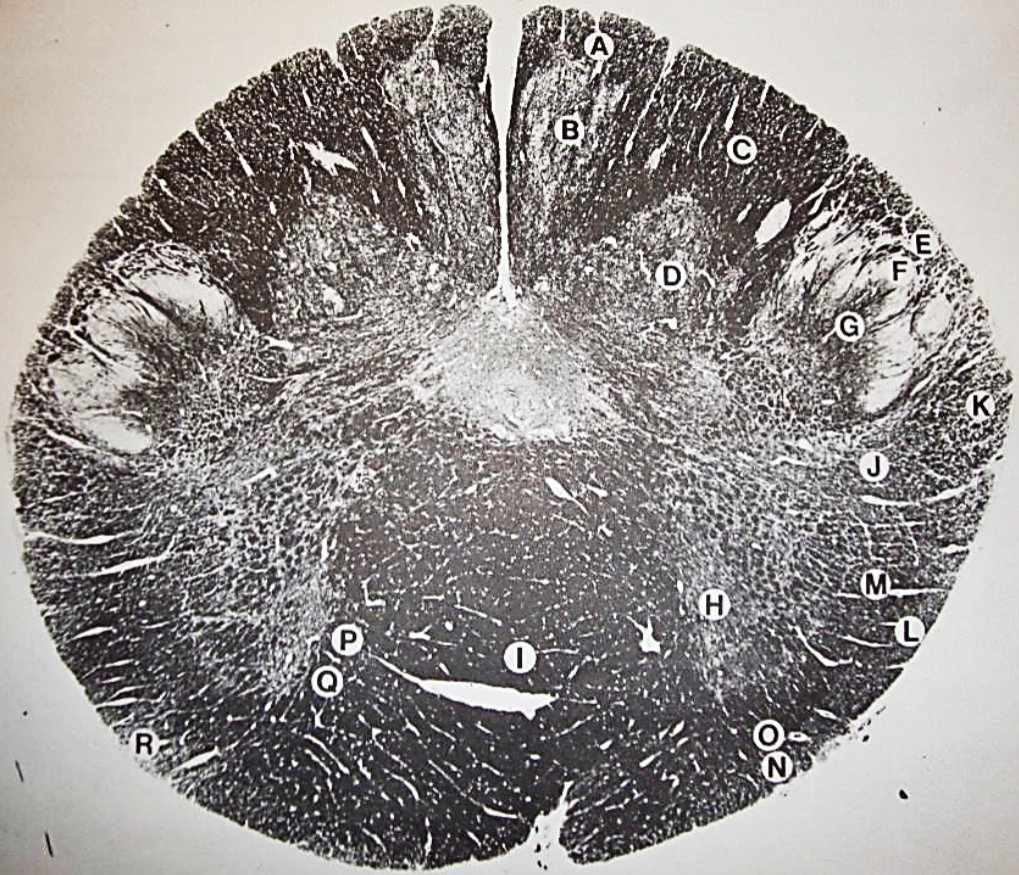

A

Fasciculus gracilis

B

gracile nucleus

C

fasciculus cuneatus

D

cuneate nucleus

E

spinal trigeminal tract

F+G collectively

spinal trigeminal nucleus

H

accessory nucleus

I

pyramidal decussation

J

rubrospinal tract

K

posterior spinocerebellar tract

L

anterior spinocerebellar tract

M

lateral spinothalamic tract

N

anterior spinothalamic tract

O

lateral vestibulospinal tract

P

medial longitudinal fasciculus

Q

tectospinal tract